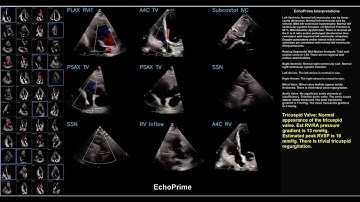

Revolutionizing Cardiology: How EchoPrime AI is Transforming Echocardiogram Analysis